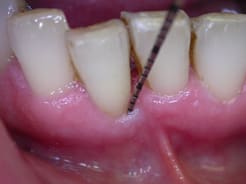

pffff....encore gourré!

resultat a 1mois, fremissement...

par contre je suis persuadé qu'il ne faut pas sonder pas irriguer plus qu'il ne faut surtout si comme dans le cas ou celui de Carole la composante occlusale prend le dessus sur la composante infectieuse .. Si abcès en urgence atb probabiliste de type metronidazole ...pas de tests . J'ai mis volontairement la sonde sur la photo pour montrer qu'à 6 mois seulement j'avais sondé pas avant.au niveau muqueux c'est cicatrisé mais au niveau osseux il faut encore 3 mois au moins